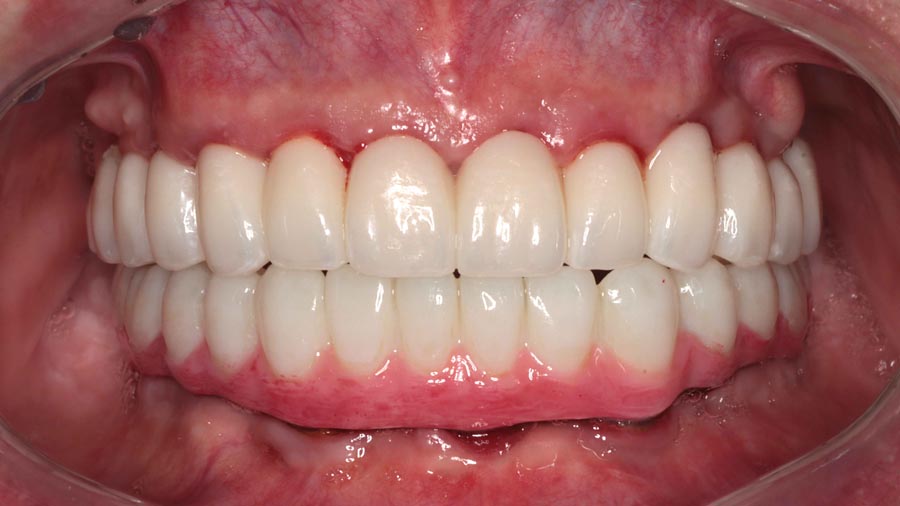

Final prostheses, intraoral, frontal. Homecare is still a problem. The final restorations are much kinder to the tissues and we hope this will resolve some of the inflammation.

Post-treatment panoramic image. This treatment is as good as humans can do in 2025. This patient was undecided whether to keep his teeth. We gave him the chance to consider this option but later he decided to have full mouth implants. We changed gears and were able to deliver World Class outcomes. We continue to encourage better homecare. This patient is from out of state so we haven’t seen his tissues in almost a year.